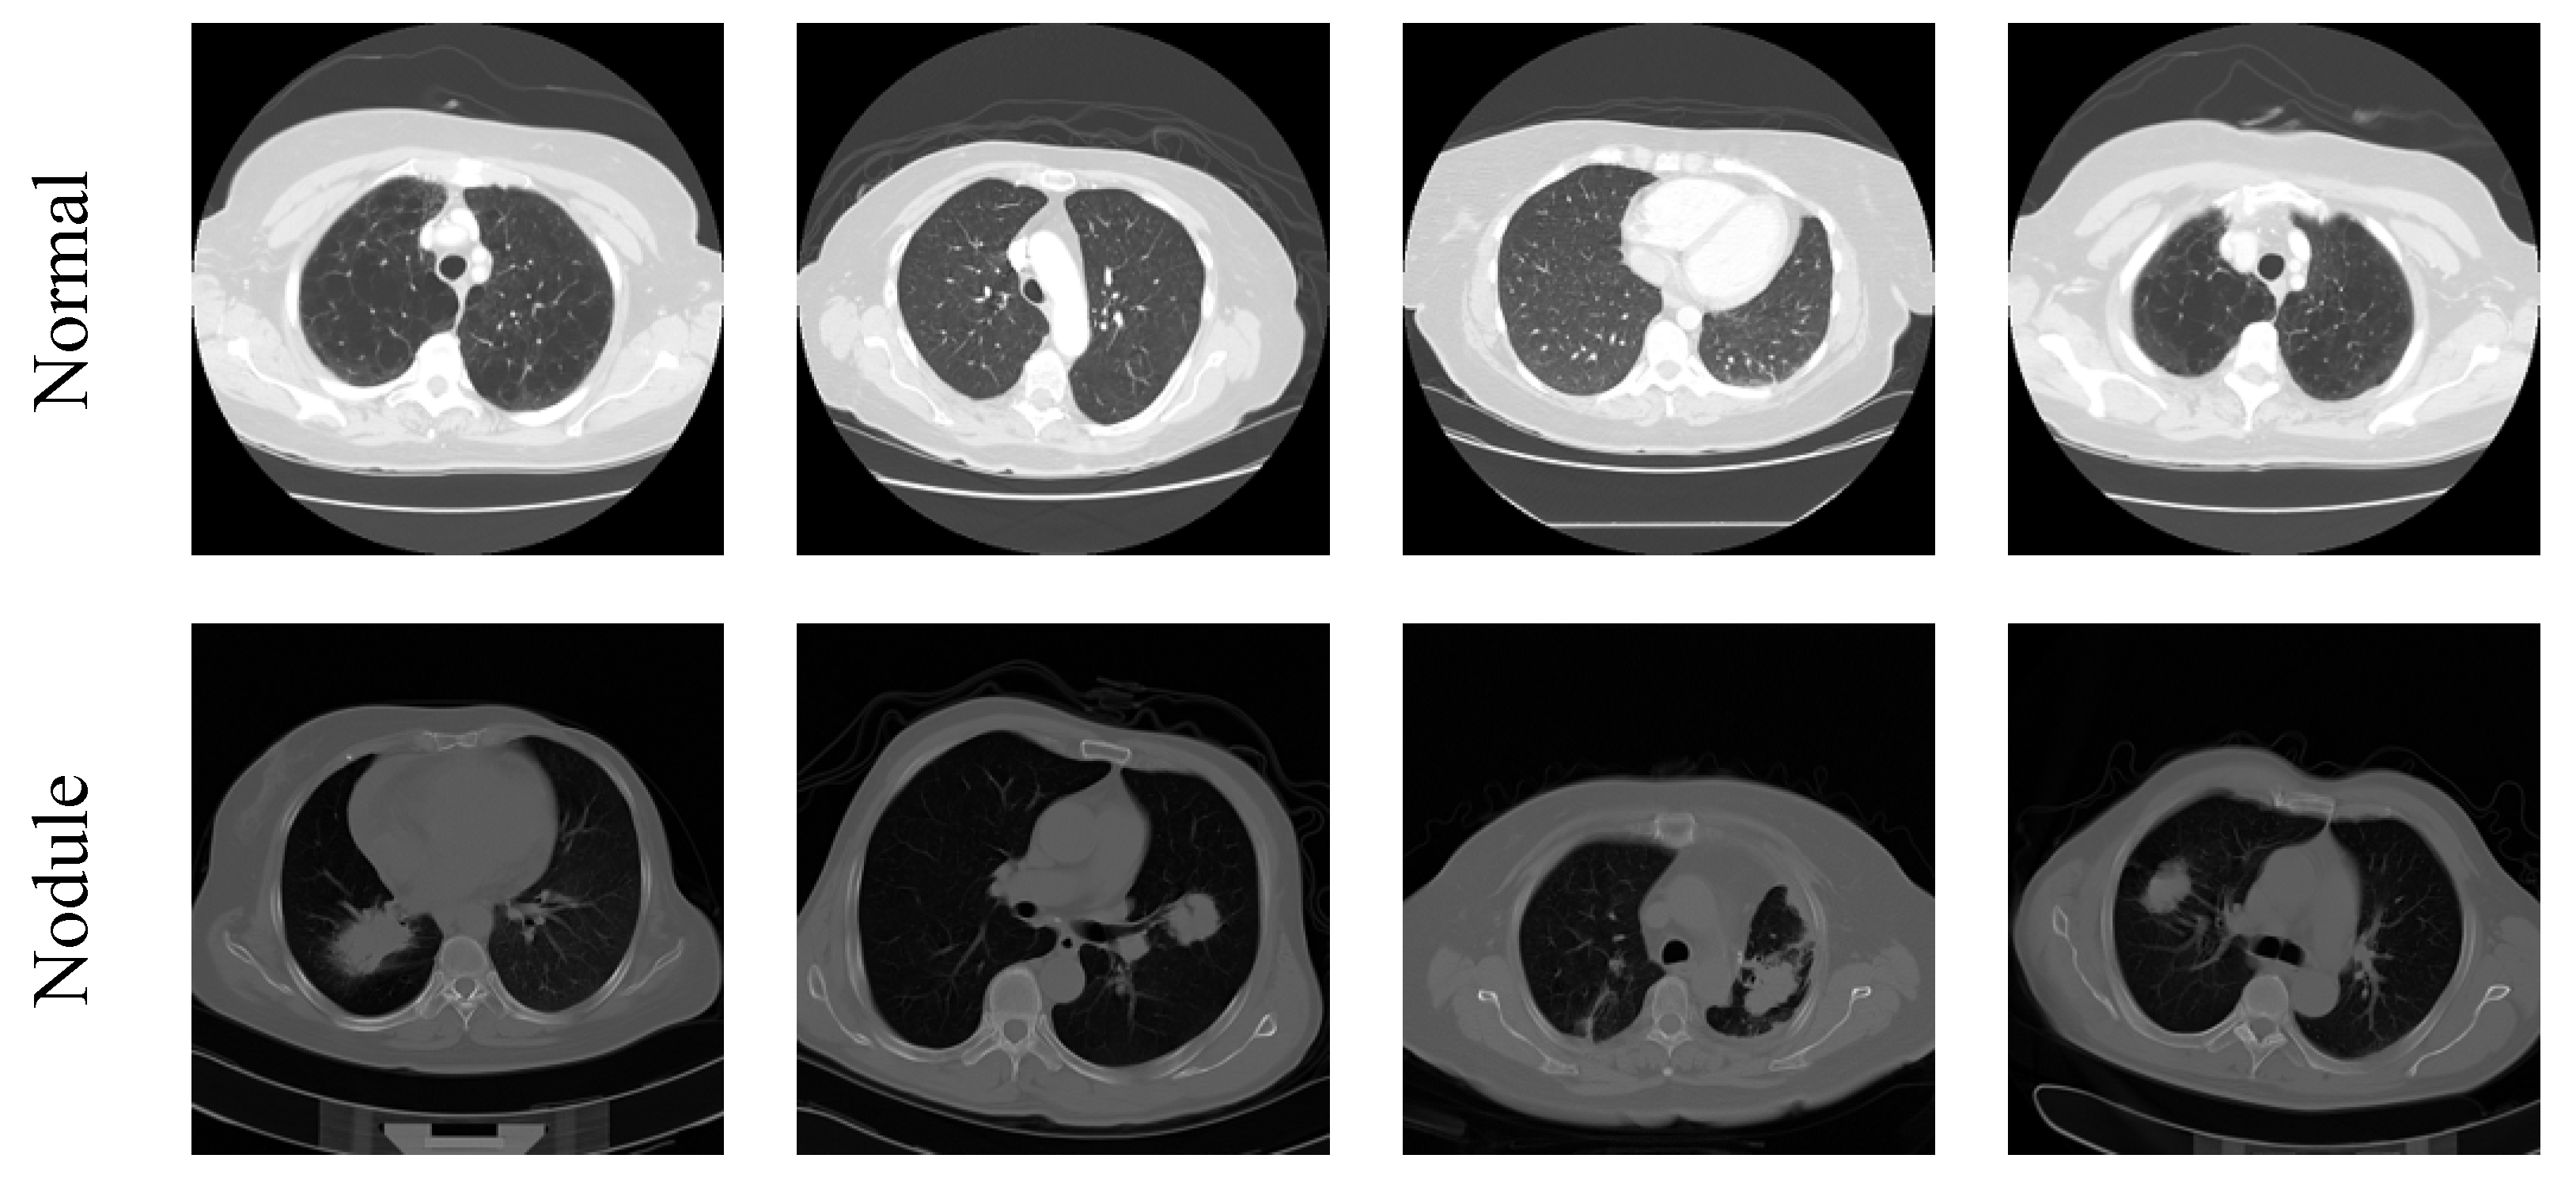

3.1. Image Database Preparation